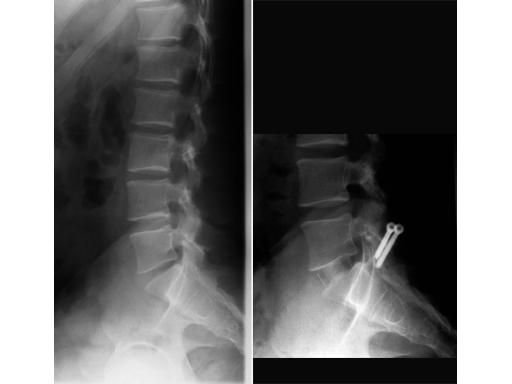

Clinical Case

31-year-old man, lateral, pre- and postoperative x-rays.